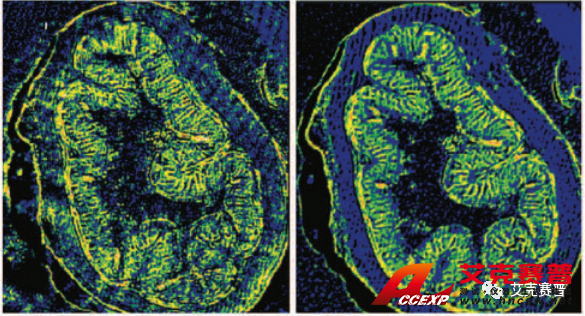

圖2顯示了布魯克已獲得專利的空間相干性抑制技術(shù)在采集激光紅外圖像時(shí)起到的改善作用。在左側(cè)的圖a和圖c中,可以看到激光束的干涉條紋對(duì)成像結(jié)果的影響。圖像看起來(lái)很模糊,有條紋和斑點(diǎn)。右側(cè)的圖b和圖d中相干性抑制技術(shù)在光源處消除了空間相干現(xiàn)象,從而采集到無(wú)比清晰的圖像(未經(jīng)任何后期處理)。

圖2:布魯克的空間相干性抑制專利技術(shù)改善了使用QCL成像技術(shù)采集的紅外成像的質(zhì)量: 我們得到了(d)原本的紅外成像圖,而不是(c)中干擾的傷偽影、條紋和斑點(diǎn)I2,該成像未經(jīng)任何后期處理。